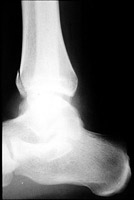

- Click on the image for a larger versionALateral radiograph of the ankle. This reveals a fracture of the anterolateral aspect of the tibia.